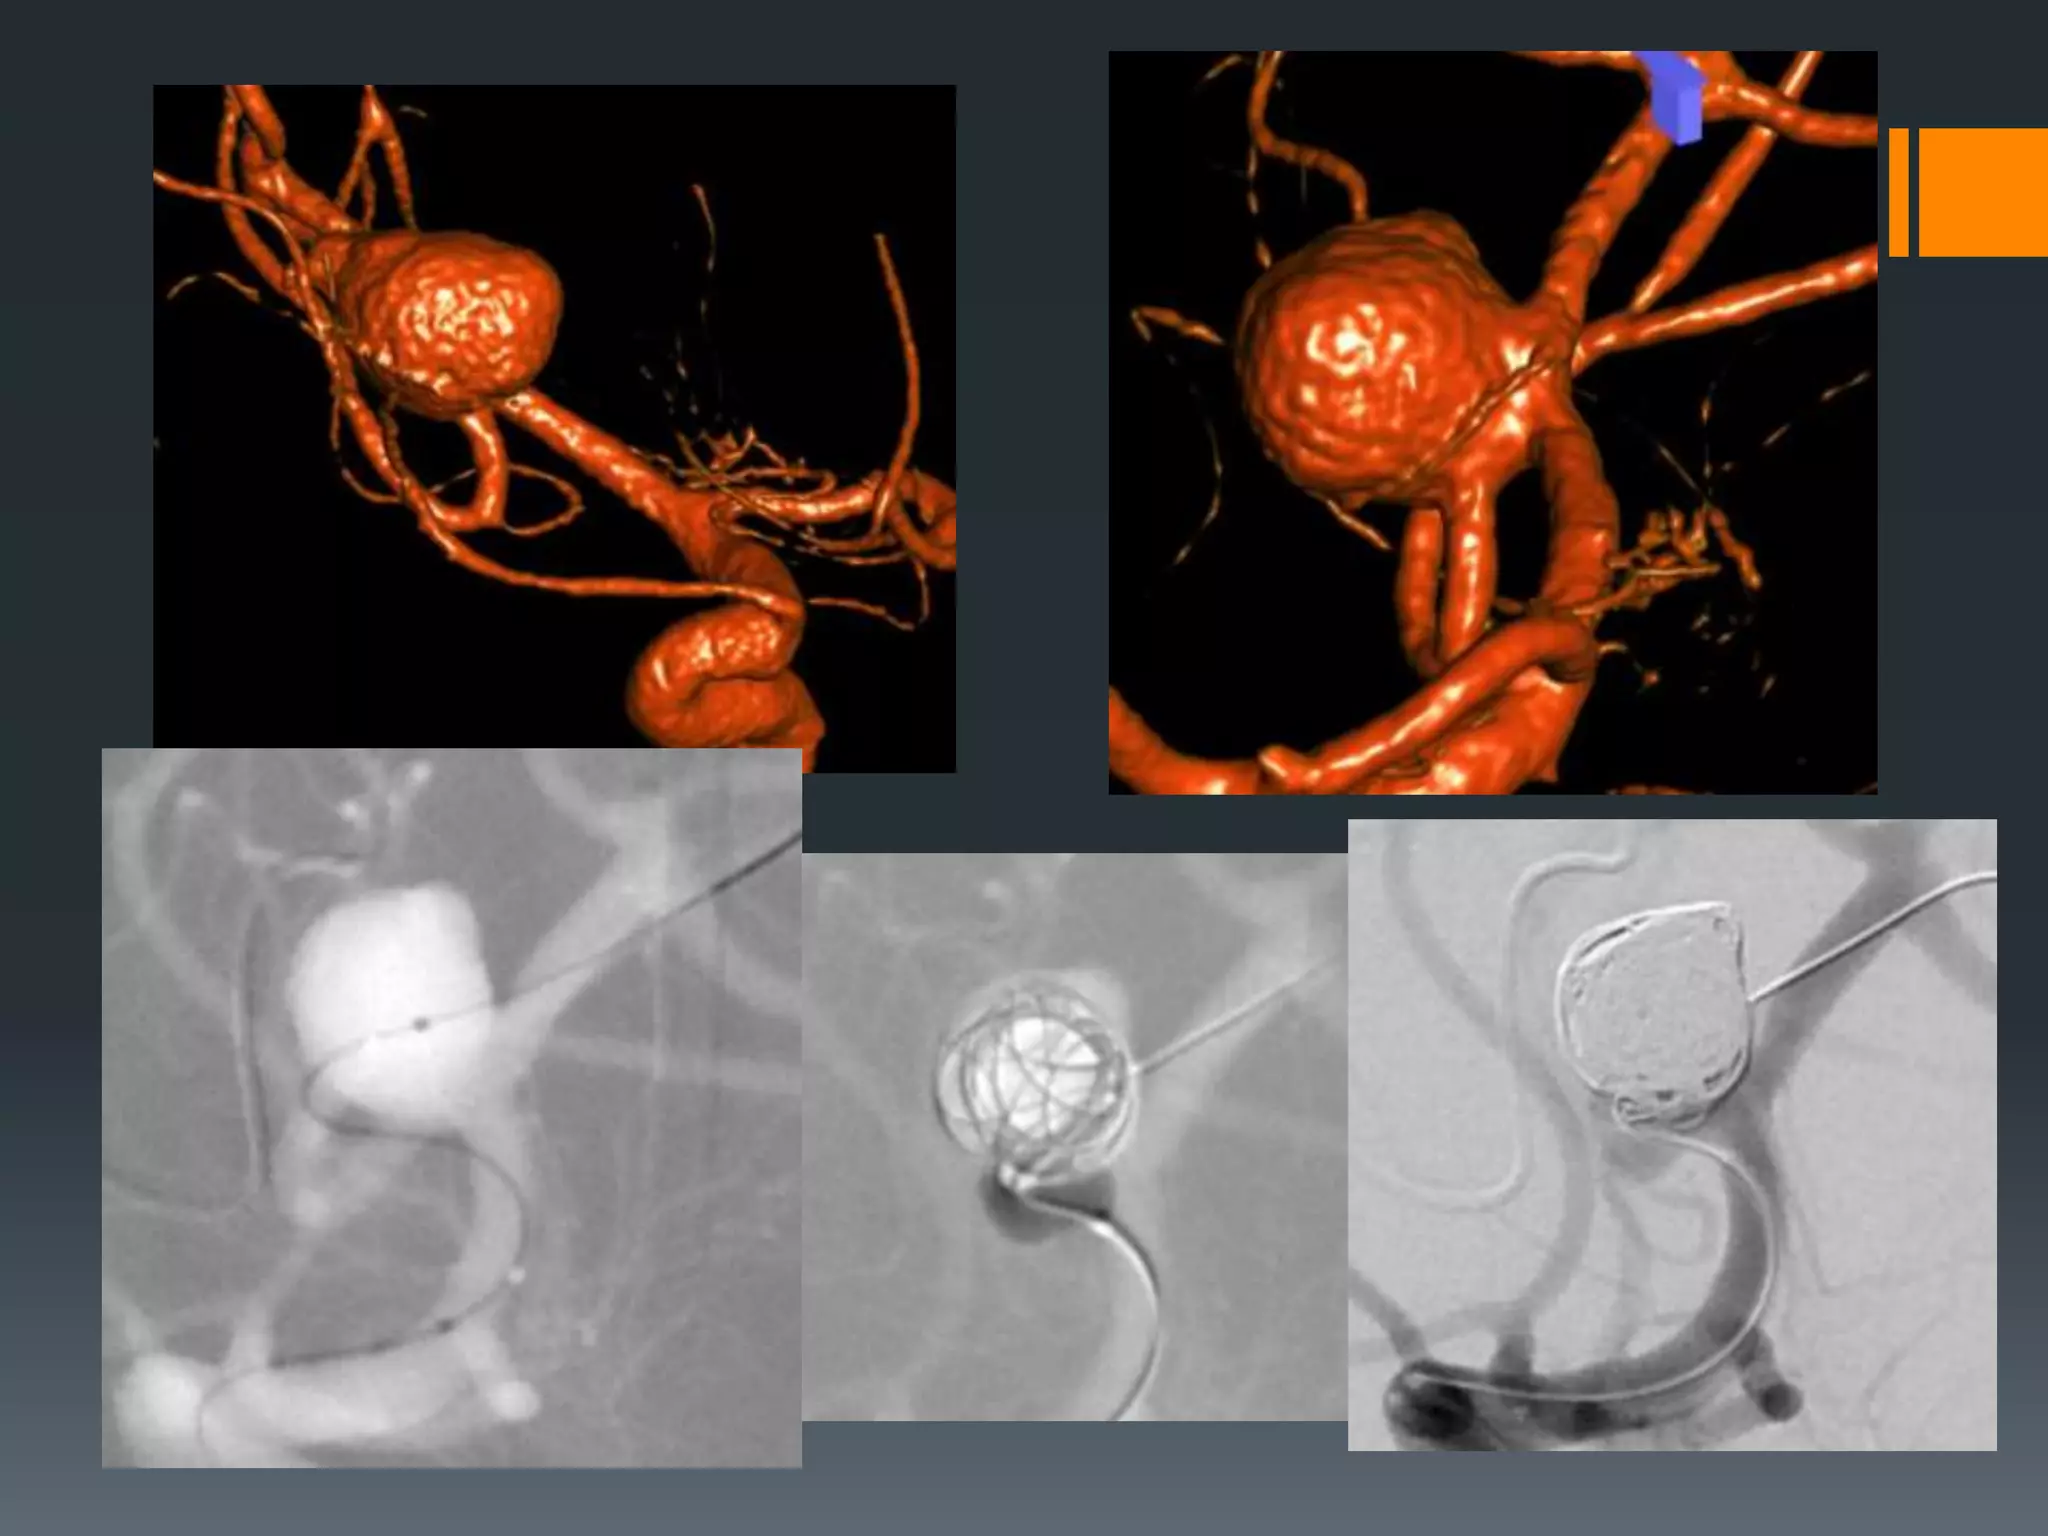

This document discusses tricks and techniques for difficult cannulations during neurointerventional procedures. It outlines strategies for accessing the aortic arch, internal carotid artery (ICA), and areas distal to aneurysms. Long sheaths, distal access catheters, and co-axial techniques are presented as options that have improved cannulation success. Guidance on sheath and catheter selection is provided for different vessel paths. The importance of catheter placement as high as possible in the ICA is emphasized. Reverse curve cannulations are also mentioned. Overall, the document stresses that careful cannulation is critical for procedural success and different strategies may be needed depending on the vessel target.